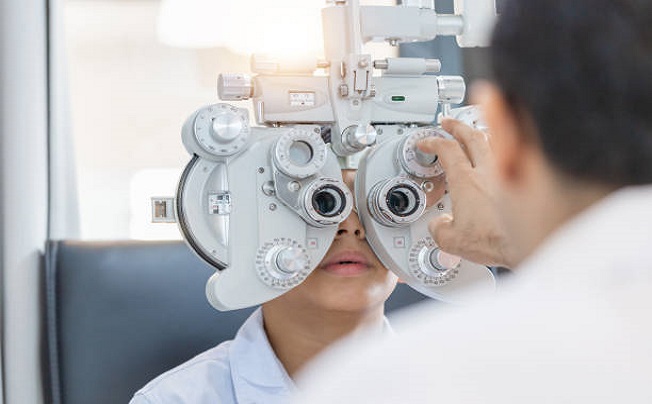

Ophthalmology

Includes diagnostic, refraction, Phacoemulsification & Vitrectomy surgical devices, therapeutic equipment & Lasers, Surgical Instruments and optical lab tools